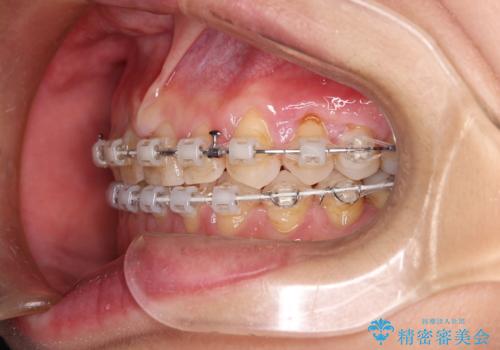

【審美装置】すきっ歯をワイヤー装置で治したい

- 矯正装置

- 審美装置

- 前歯のすきっ歯が気になるということで来院されました。今回は抜歯はしないためワイヤー矯正かインビザライン矯正のどちらでも治療可能でしたが、患者さまのご希望により表のワイヤー装置にて治療をおこないました。

前歯に隙間がいくつかあったため、今回は上下でゴムかけを行いスペースを埋めるための力をかけて閉じました。もう少し早く終了する予定でしたが、ブラッシング不良による歯肉腫脹があり、一部スペースクローズに時間がかかりました。